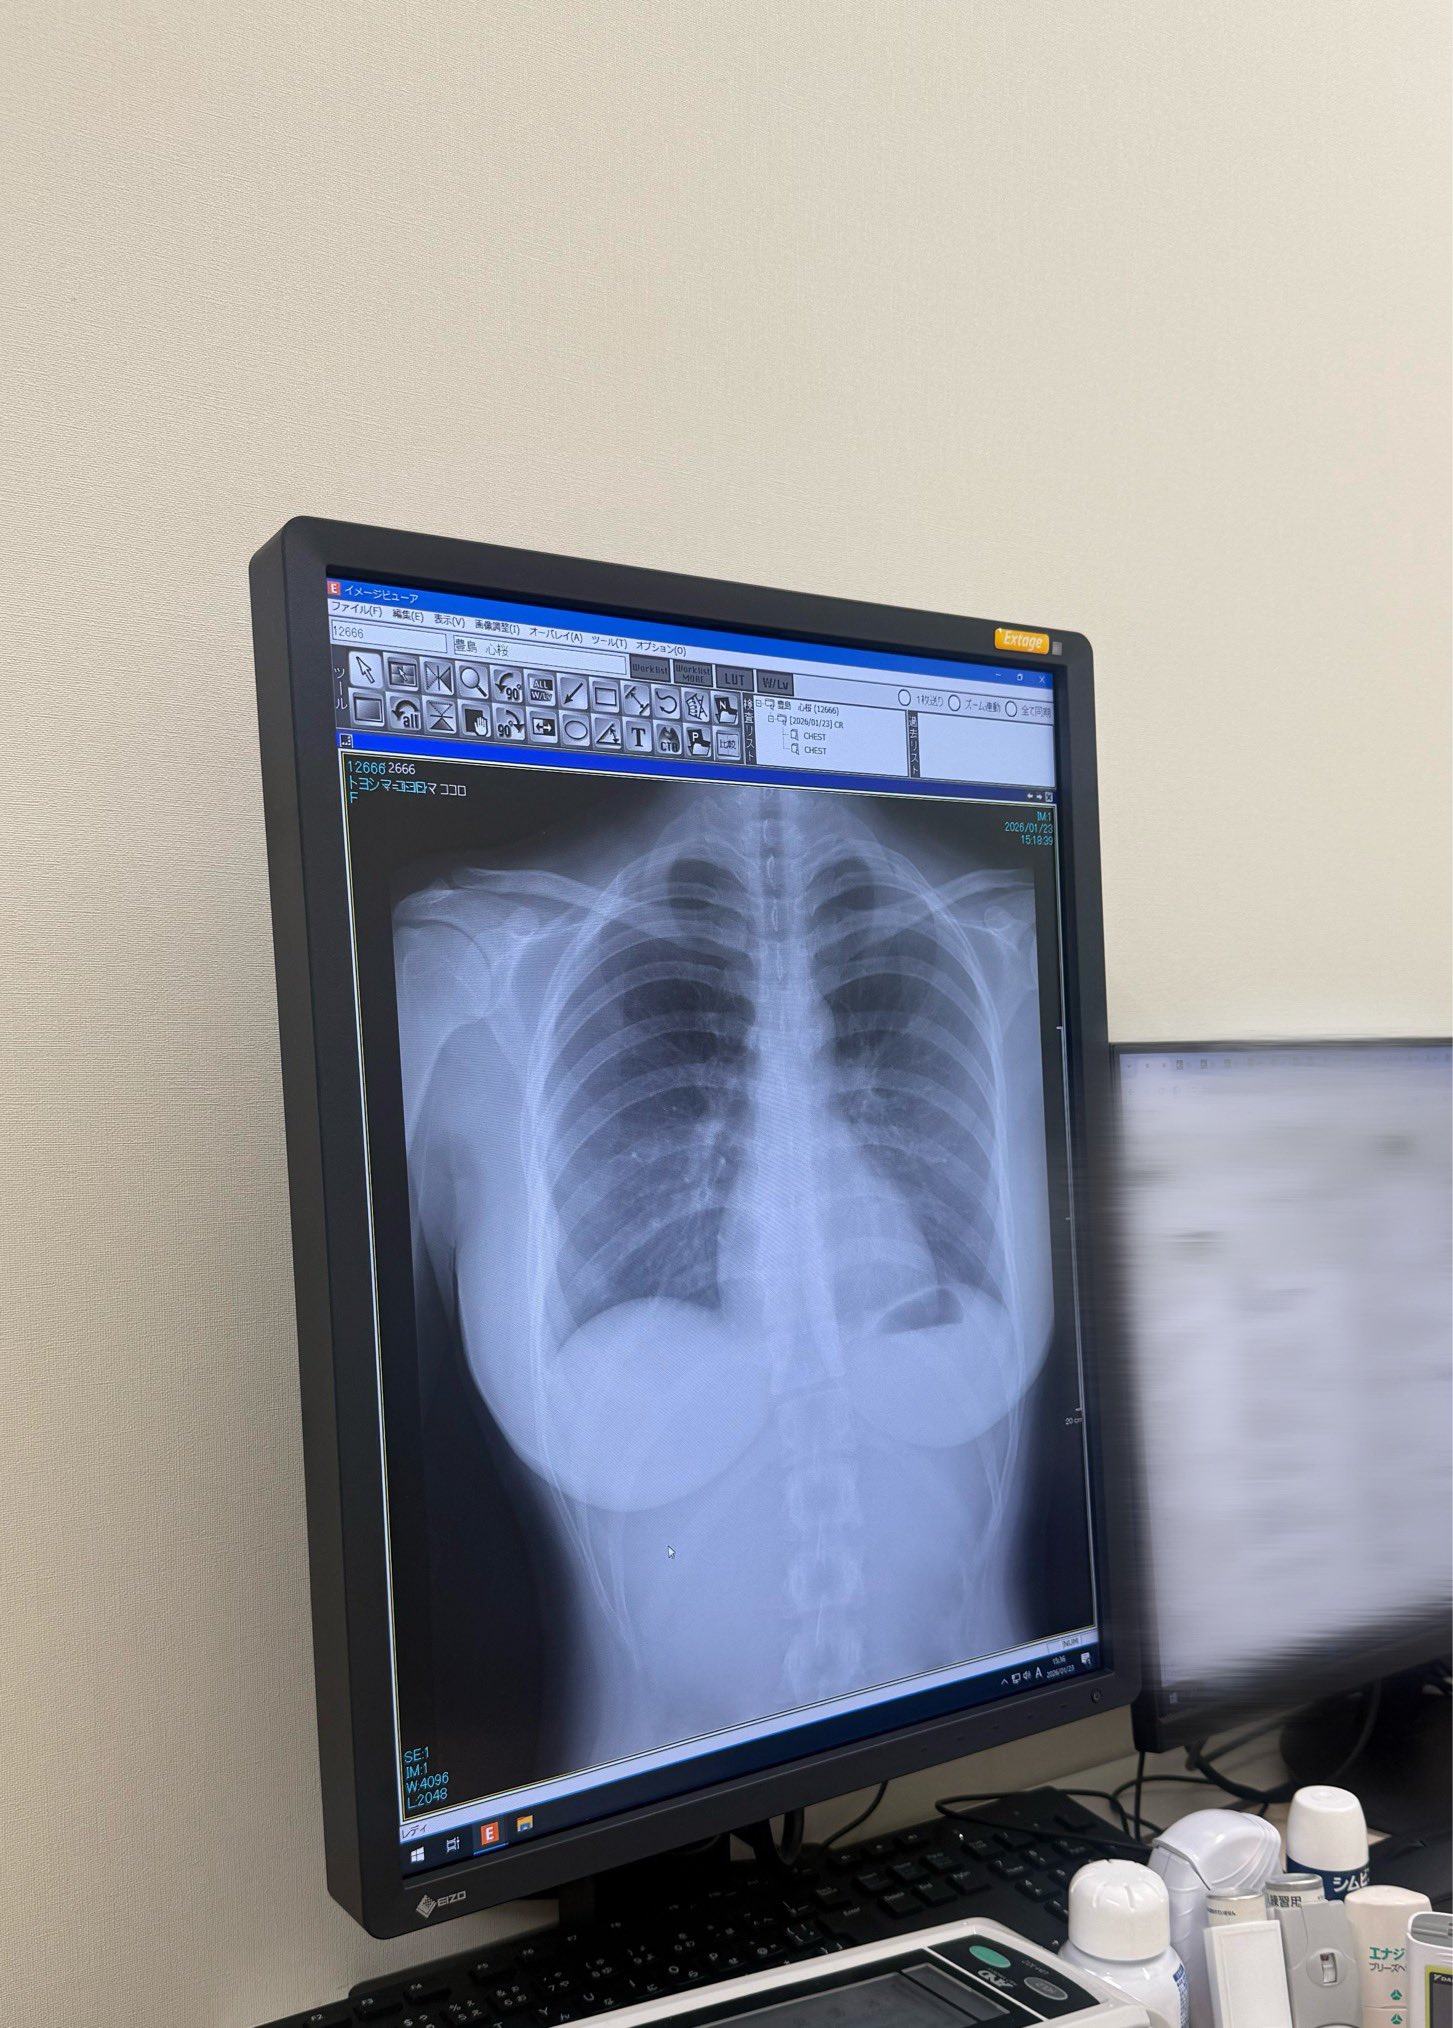

爆乳はレントゲンにも映るんだな

豊島 心桜(こころ)さんのスケスケおっぱい

名前映っとる!

レントゲンに映ってる肩関節や背骨の突起や肋骨の立体的な構造がこんな綺麗な人の身体に収まってるの感動する

肋骨が美しく見える気がする

くびれの形になってるんだな

恋人でもなかなか見る機会ないよ背骨のカーブとか

シリコンはばっちり像影されるけど最近主流の豊胸は脂肪注入だからレントゲンでもわからないってプロがこれに淫リツしてた

進化してるんだなオッパイも

レントゲンよく見ると背骨ってまっすぐじゃなくてゆるくS字になってるんだな

側面から見るとそうだが正面からはまっすぐなのが普通だぞ

加齢とか生まれつきとかで左右にS字になる人もまあまあ居るけど程度が酷ければ脊柱側弯症という病気になる

スレ画くらいなら異常ってほどではないし何も問題はないけどお婆さんになった時にはもっと曲がってるかもな